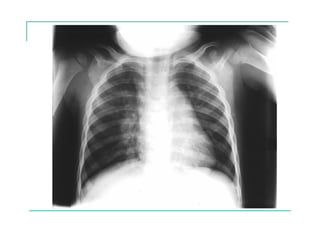

EXAMEN FÍSICO

- Aumento del diámetro antero posterior del tórax

- Tiraje, uso de músculos accesorios

- Aleteo nasal

- Hipocratismo digital

- Cianosis

- Signos de malnutrición

AUMENTO DEL D.A.P. DEL TORAX

EVOLUCIÓN RADIOLÓGICA